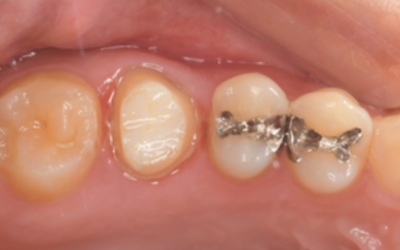

移植手術後

右上6抜歯1ヶ月後、移植手術を行った。

右下8を抜歯し右上6部に移植、縫合糸で固定した。

移植手術後、治癒に異常を認めなかったため、移植2週間後に根管治療を行った。